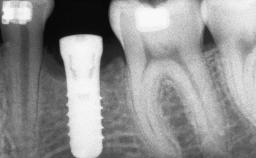

# of Implants 8

Type of Implants Reduced-Diameter|Two-Piece

Bone Augmentation Horizontal|Sinus Floor Elevation|Staged|Vertical

Augmentation Materials Autogenous chips|Autogenous block(s)

Bone Volume Deficient vertically or deficient vertically AND horizontally